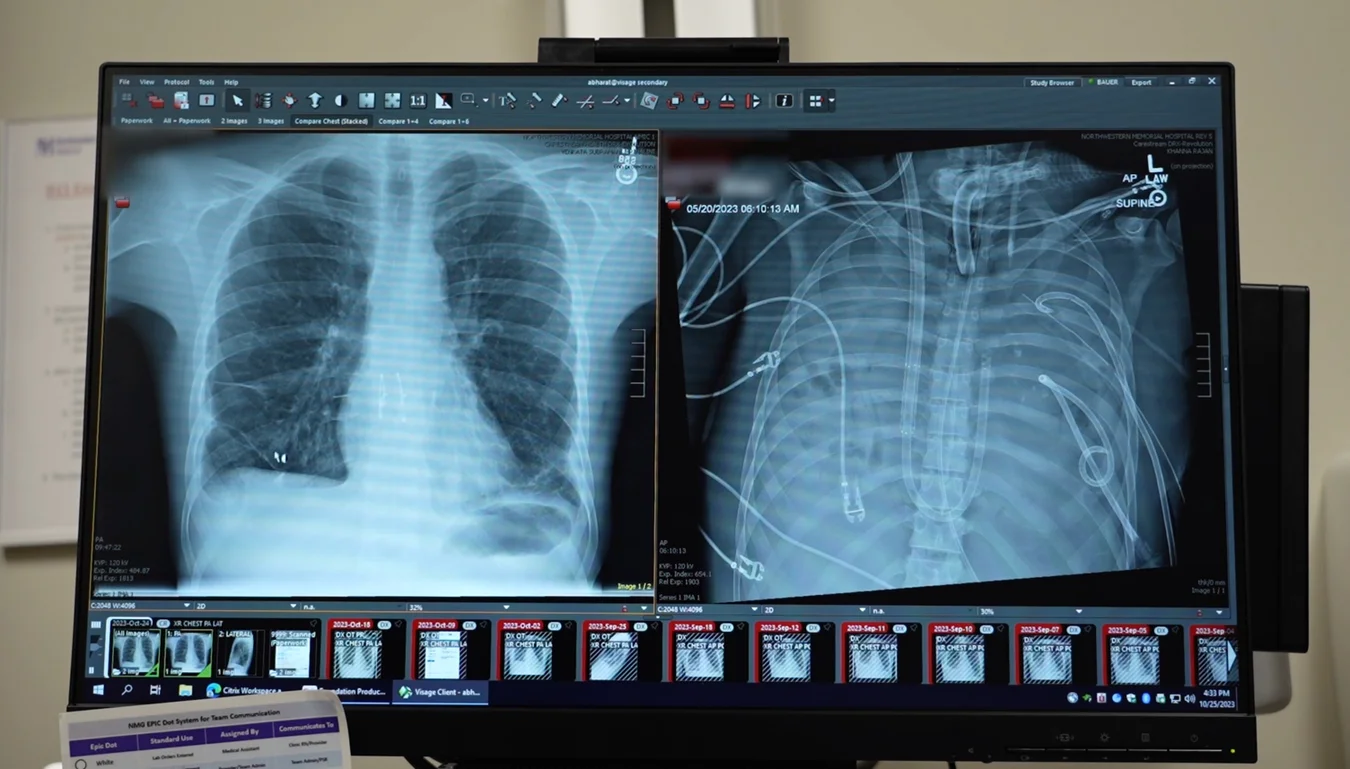

图片来源:Northwestern Medicine

患者是一名 33 岁男性,因流感继发细菌性肺炎,导致急性呼吸窘迫综合征(ARDS)。他的双肺在感染与炎症冲击下迅速恶化,并逐步引发心、肾功能衰竭。常规治疗已无法控制病情,肺移植成为唯一生存希望。然而,由于感染过重、全身状态极差,患者当时无法立即接受移植手术。

为破解“无肺期”的生命维持难题,医疗团队设计了一套人工肺系统,在患者完全无肺的状态下暂代肺功能,为血液供氧、清除二氧化碳、帮助维持心脏及全身的血流稳定。在切除严重感染的双肺后,患者的血压逐渐平稳,器官功能开始恢复,感染也得到控制。48 小时后,等到了匹配的供肺,团队成功为他完成了双肺移植。